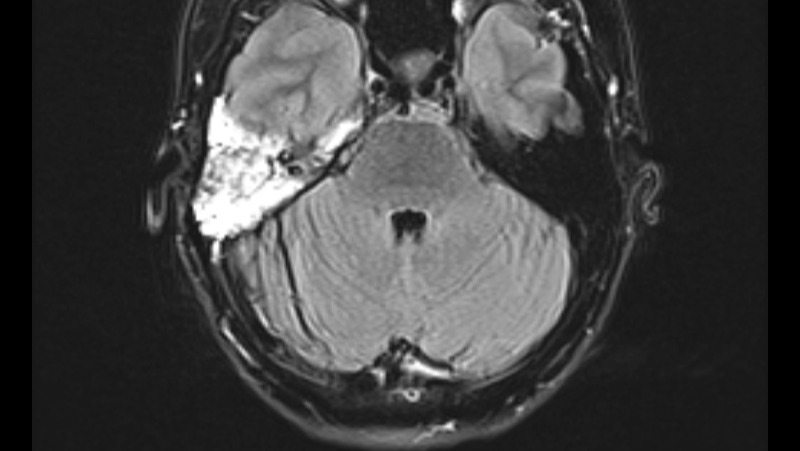

On May 25, 2022, after experiencing debilitating symptoms, I was diagnosed with an Acoustic Neuroma brain tumor.

The tumor had enveloped my auditory nerve and while small was also causing significant damage to my facial and vestibular nerves.

A retrosigmoid craniotomy to remove the tumor was performed on August 12, 2022 at Mayo Clinic in Rochester, Minnesota. This is highly invasive surgery, requiring the retraction of the cerebellum for several hours and highly skilled neurosurgeons.

Two days after my brain surgery I developed a life threatening cerebrospinal fluid leak. I endured a spinal tap without localized pain meds, repeated lumbar drains, then another cranial surgery to repair the leak. This repair involved temporarily cutting off my right ear and placing a fat graft within my skull.

Since these surgeries I have endured chronic cranial pain at levels of 4 to 6 out of 10. Depending on circumstances the pain rises to 8 or 9 out of 10 regularly. I have barely slept since the surgeries as I must take medication every 6 hours around the clock just to maintain my "normal" pain level. Because of the damage to my vestibular nerve, I needed a cane to walk until March of 2023. Because of the need to remove my auditory nerve along with the tumor, I am now permanently deaf on my right side. I also have constant roaring tinnitus, and a significant build up of unresolved fluid.

I will need a yearly brain mri to monitor for tumor regrowth. My neurologist has recently prescribed physical therapy to begin late November 2023. He believes the severing of a major nerve in my neck is responsible for the majority of the chronic pain, and that massage may relieve it to a degree without the need for additional medication.